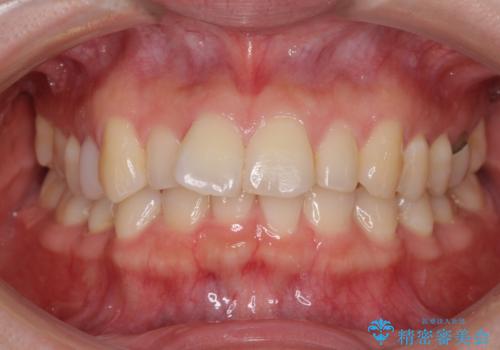

先天欠損のある歯列 インビザライン矯正

- 上顎前歯の突出感を気にして来院された患者様です。

下顎前歯2本が先天欠損しており、上顎歯列に対して、下顎歯列がアンバランスに小さい状況でした。

左右上顎側切歯2本が矮小歯であるため、上顎の抜歯ではなく、IPR(歯と歯の間を削る)と歯列全体の後方移動によってバランスを整えることとしました。

目立ちにくい装置を希望されたため、インビザラインにて治療を行うこととしました。